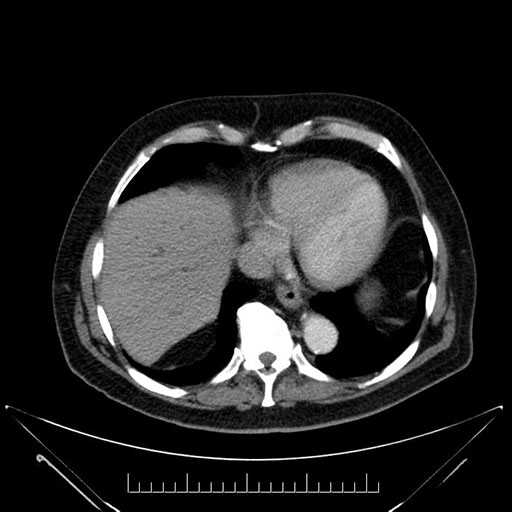

Imaging Analysis

Look through the patient's CT scan to identify any areas of concern for the necessary procedure.

Based on your CT findings, which issue(s) would give reason for "planned slowing down moment(s)" in this case?

Considering a standard Whipple procedure, what step(s) of the operation would you do differently in this case?